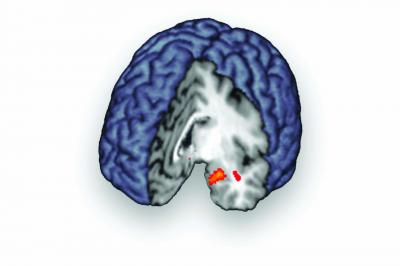

Brain scans made during these moments showed opioid release, measured by looking at the availability of mu-opioid receptors on brain cells. The effect was largest in the brain regions called the ventral striatum, amygdala, midline thalamus, and periaqueductal gray – areas that are also known to be involved in physical pain.

"Individuals who scored high for the resiliency trait on a personality questionnaire tended to be capable of more opioid release during social rejection, especially in the amygdala," a region of the brain involved in emotional processing, Hsu says. "This suggests that opioid release in this structure during social rejection may be protective or adaptive."

The more opioid release during social rejection in another brain area called the pregenual cingulate cortex, the less the participants reported being put in a bad mood by the news that they'd been snubbed.